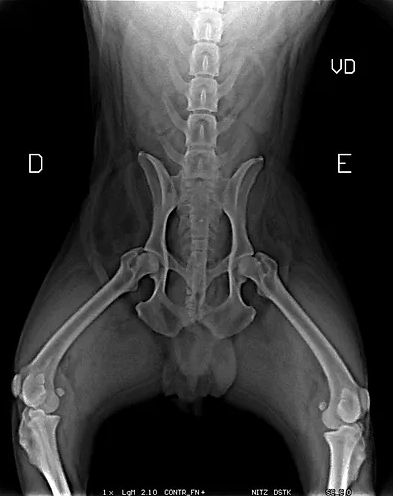

Radiologia Digital Direta / Digital Radiography

iPad com tela Retina Apple® possibilita a visualização das imagens com maior qualidade diagnóstica.